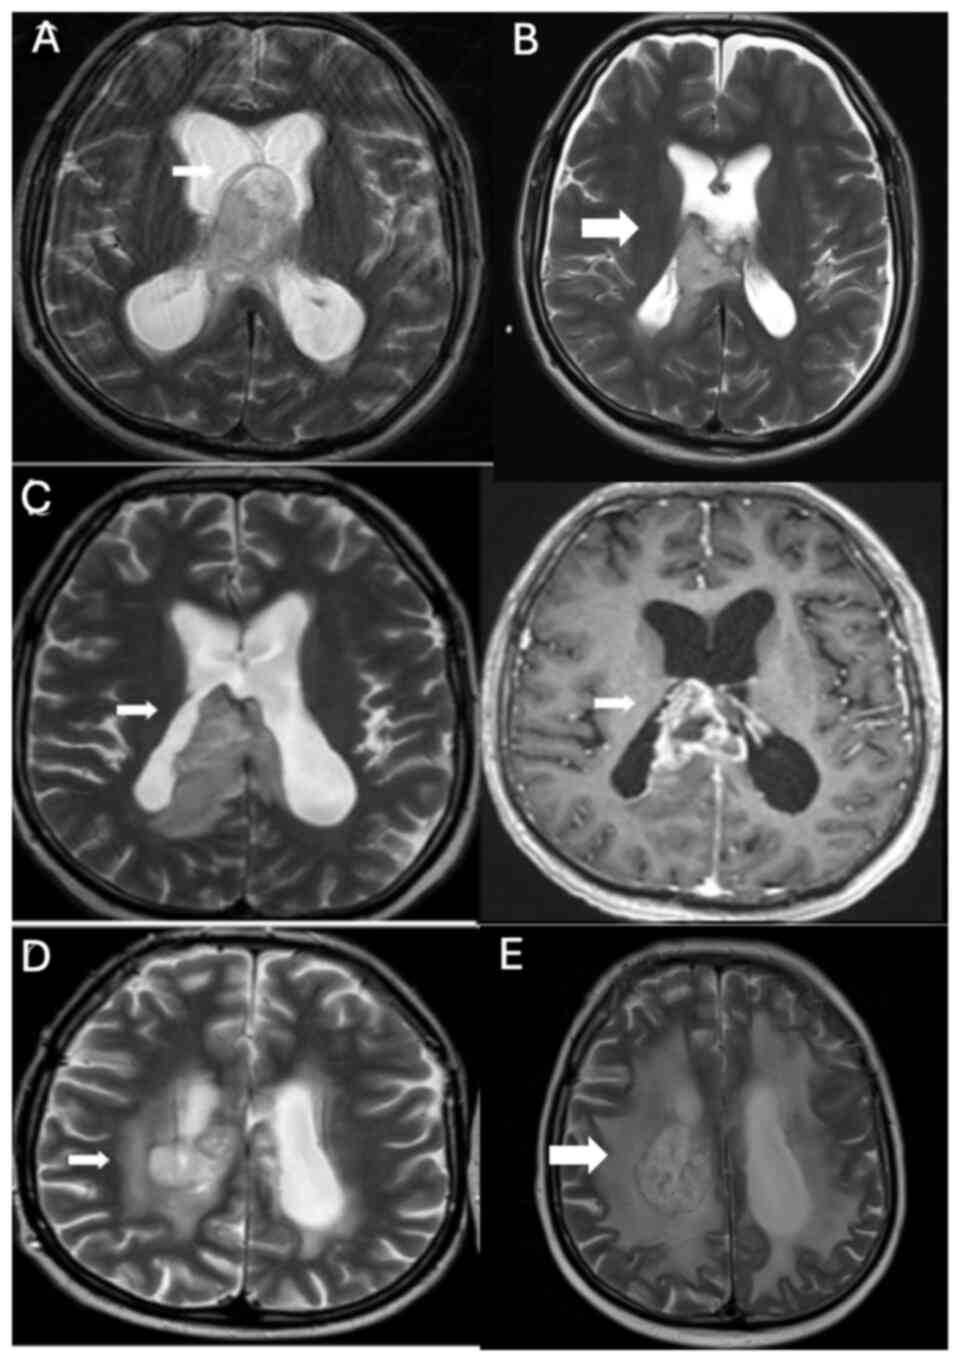

A 45-year-old female patient with a hypervascular mass lesion (Fig. 1A), located close to the right parietal vertex, underwent surgery at The Department of Neurosurgery, Hacettepe University Faculty of Medicine (Ankara, Turkey), in September 2018 (Fig. 1A and B), and the pathology indicated glioblastoma, isocitrate dehydrogenase (IDH) wild-type (GBM). Immunohistochemical analysis was performed on paraffin-embedded tissue samples using primary antibodies against ATRX, IDH1, glial fibrillary acidic protein (GFAP), Ki67 and p53. The Ki-67 proliferation index was 30–35%, ATRX expression was preserved, GFAP staining was positive and p53 was overexpressed in 80% of the tumor cells. The patient received 60 Gy intensity-modulated radiotherapy simultaneously with temozolomide, and then adjuvant temozolomide treatment was initiated. The patient completed the first course of temozolomide treatment in December 2018. Progression was detected on the magnetic resonance imaging (MRI) captured afterwards (Fig. 1C), and the patient underwent surgery again in January 2019 (Fig. 1D). The pathology was compatible with GBM, and postoperative changes and a residual mass were revealed on the postoperative MRI. The first course of treatment with nivolumab (200 mg every 2 weeks) was started in January 2019. After the second course of nivolumab, spinal MRI was performed because the patients' lower back pain was severe. After a collapse fracture was detected in multiple-level vertebrae, in February 2019, L2-L4 vertebroplasty surgery was performed. The third cycle of nivolumab began in April 2019. The treatment of the patient was discontinued after the third cycle due to severe pneumonitis. In June 2019, a cranial MRI (Fig. 1E) showed an increase in the size of the right parietal lesion, perilesional edema with heterogeneous contrast enhancement and a lack of increased perfusion on the cerebral blood volume map, indicative of pseudoprogression. These findings extended to the right parietal periventricular area and involved the corpus callosum splenium.

Figure 1.

(A) In September 2018, before surgery, a hyperintense expansile lesion with prominent enhancement was observed in the right paracentral lobule on axial T2-weighted imaging and post-contrast axial T1-weighted imaging (white arrows). (B) Postoperative MRI after the first surgical resection in September 2018, confirming GBM pathology (white arrow). (C) MRI after the first course of temozolomide in December 2018, showing progression (white arrow). (D) Postoperative MRI after the second surgery in January 2019, revealing residual GBM and postoperative changes (white arrow). (E and F) The right parietal lesion exhibited an increase in size, perilesional edema and heterogeneous contrast enhancement (white arrows). There was no evidence of increased perfusion on the cerebral blood volume map (not shown), indicating pseudoprogression. MRI, magnetic resonance imaging; GBM, glioblastoma multiforme.

The treatment of the patient was switched to bevacizumab-irinotecan (10 mg/kg bevacizumab, 125 mg/m2 irinotecan, every 2 weeks) in July 2019; however, after the second dose of bevacizumab, the patient was admitted with gastrointestinal bleeding, and based on colonoscopy, colitis was detected. In December 2019, an MRI (Fig. 1F) showed no evidence of tumor progression, but rather pseudoprogression due to radiation necrosis. The patient died in October 2020.